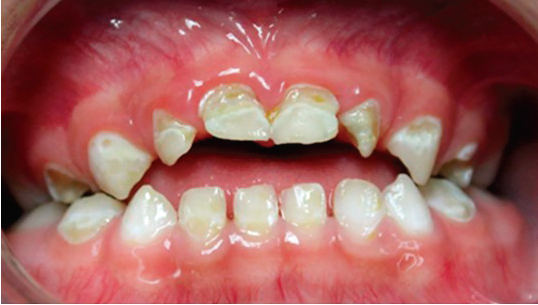

Se llevó a cabo la exploración extraoral y se logró apreciar una ligera asimetría facial, en las fotografías de perfil se ve la implantación de la oreja por debajo de lo normal (figura 1). Al hacer la exploración intraoral se encontraron sobre la superficie de todos los dientes manchas de color amarillento con descalcificaciones y lesiones cavitadas, al complementarse con la historia clínica y antecedentes patológicos, se determinó el diagnóstico de hipoplasia del esmalte generalizada (figura 2).

Figura 2. Examen clínico extraoral.